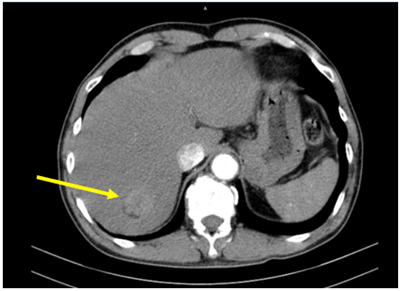

UNG THƯ BIỂU MÔ TẾ BÀO THẬN

Ung thư thận là loại ung thư thường gặp đứng thứ 14 trên toàn cầu, với hơn 430.000 ca mới được chẩn đoán vào năm 2020, và 434840 ca mắc trên toàn cầu vào năm 2022. Tỷ lệ mắc thay đổi theo khu vực địa lý, cao hơn ở châu Âu và Bắc Mỹ. Ung...